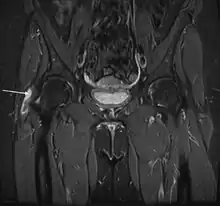

X-rays, ultrasound and magnetic resonance imaging may reveal tears or swelling. But often these imaging tests do not reveal any obvious abnormality in patients with documented GTPS.[5]